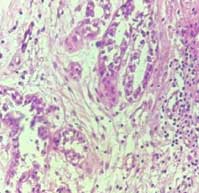

हिस्टोपॅथॉलॉजी ही अशी प्रक्रिया आहे ज्यामध्ये शरीरातून घेतलेल्या ऊतींच्या (टिश्यू / Biopsy) नमुन्यांची सूक्ष्मदर्शकाखाली (Microscope) तपासणी केली जाते.

या तपासणीत ऊतींच्या पेशींची रचना, आकार, बदल आणि असामान्य पेशींची उपस्थिती पाहून आजाराचे अचूक निदान केले जाते.